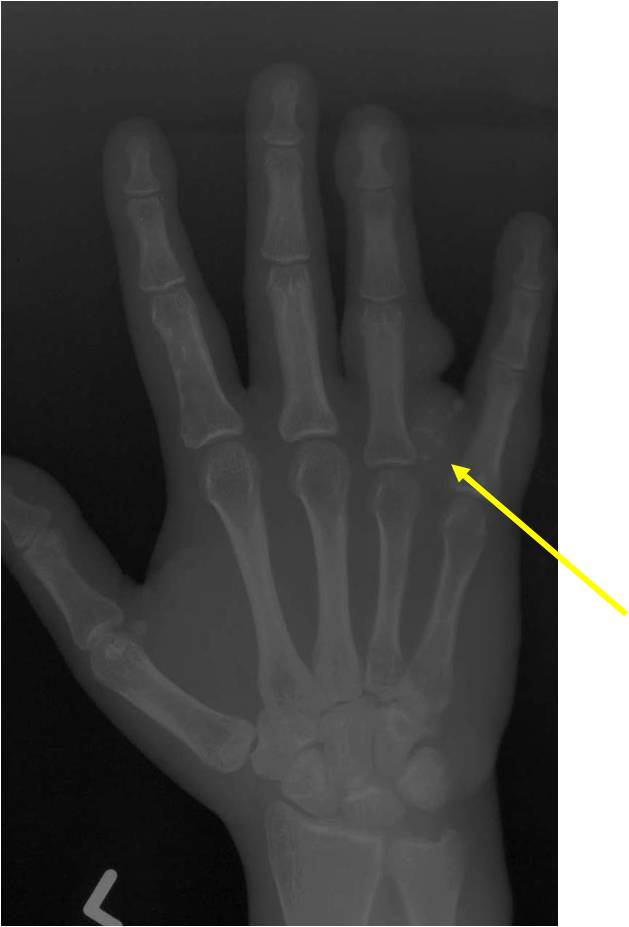

Radiographic Presentation

- Localized, radiolucent defect usually with punctate calcifications

- Calcifications are typical but not always present

- Matrix may demonstrate various degrees of calcification

- Calcifications are stippled, punctate, popcorn like calcifications and “Ring and Arc” calcifications

- Cartilage tumors grow in a lobular manner. The perimeters of the lobules undergo

- enchondral ossification that may calcify. If the entire perimeter of the lobule calcifies it appears

- radiographically as a “Ring”. If a portion of the perimeter of a lobule calcifies it forms an “Arc” on

- an X-ray.

- May be located centrally or eccentrically

- Grows eccentrically or concentrically (phalanges)

- Cortex may be scalloped and thinned in the phalanges

Plain X-Ray:

- Geographic lytic lesion

- Central often metaphyseal in long bones

- Can be eccentric also

- Expansile remodeling with thinned cortex

- Chondroid matrix with calcifications in majority of tumors

- Approximately 20% have limited or no calcifications